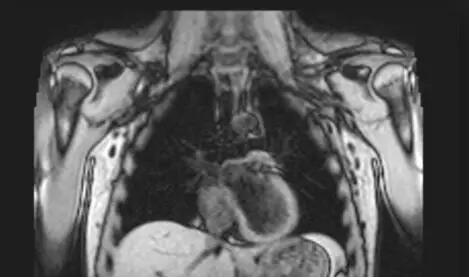

No.4 磁共振成像(MRI)

无电离辐射,适用于软组织滑膜、血管、神经、肌肉、肌腱等检查,对于肺脏这种含气组织并不敏感,因此在肺部原发灶诊断方面的作用不如CT。在肺癌患者中主要用于评价和发现是否存在脑转移和骨转移。